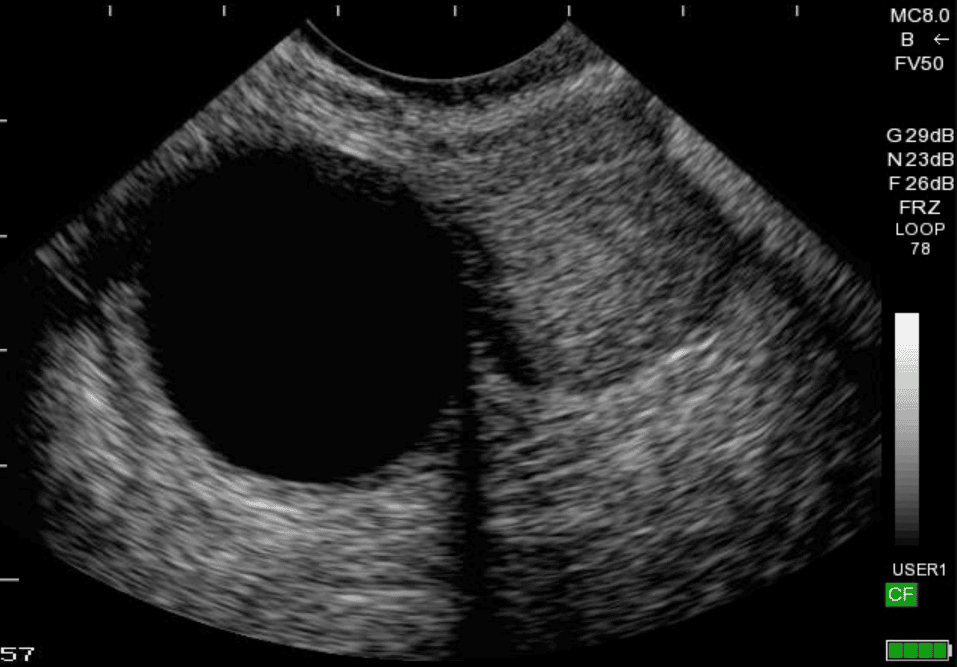

Hiện nay, tỷ lệ xuất hiện những khối u nang xuất hiện trong buồng trứng ở nữ giới ngày một tăng cao. Bệnh phát triển âm thầm và không có bất kì một triệu chứng hay dấu hiệu rõ ràng nào nên chị em cần lưu ý thực hiện khám phụ khoa định kỳ ít nhất 6 tháng/lần.

U nang buồng trứng

Hình ảnh siêu âm u nang buồng trứng